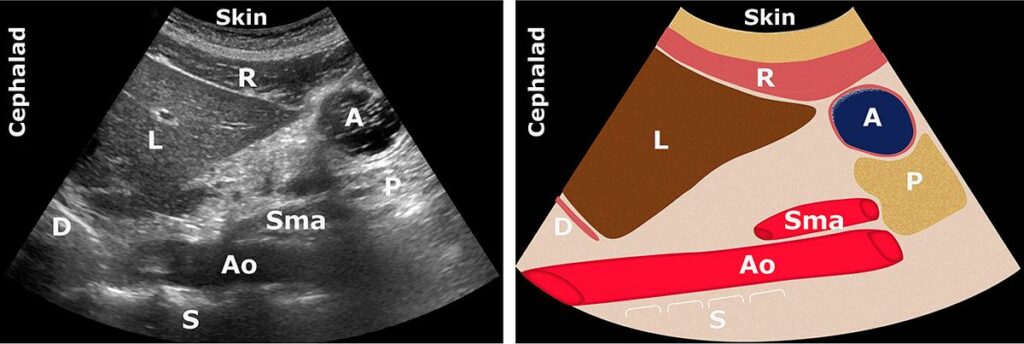

A: Antrum; Ao: Aort; C: Kolon; L: Karaciğer; P: Pankreas; SI: İnce bağırsak; Sma: Süperior

mezenterik arter; Smv: Süperior mezenterik ven

Mide antrum

Sonografik incelemeye en uygun olanıdır ve tüm midenin içeriğini doğru bir şekilde yansıtır.

Karaciğer (önde) ve pankreas (arkada) arasındadır.

İçi boş karakteristik 5 katmanlı duvarı vardır.

Genellikle yüzeysel yerleşimlidir (3-4 cm)

Önemli belirteçler

- Karaciğerin sol lobu

- Pankreas

- Aort